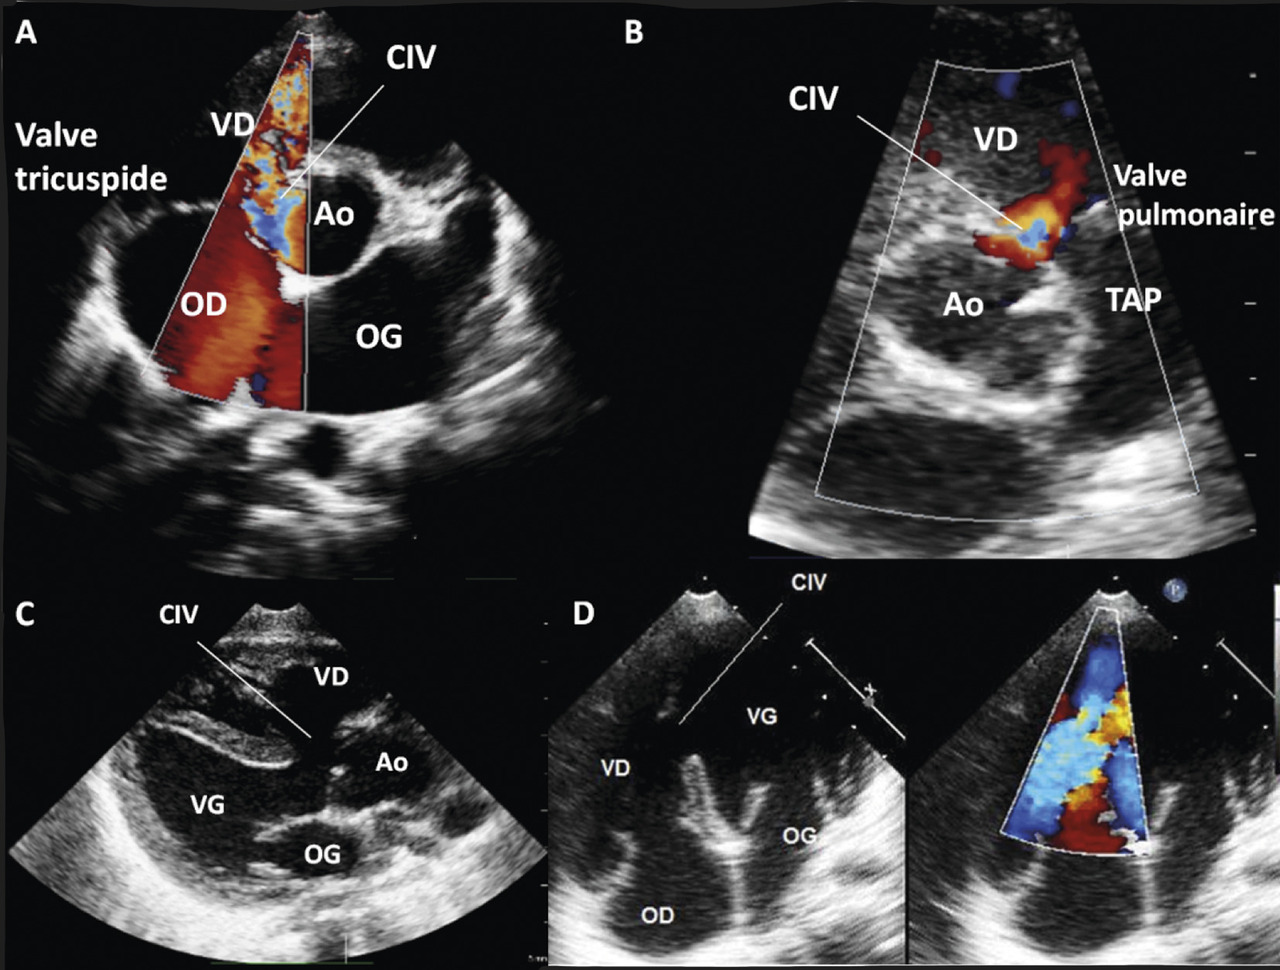

On classe également les CIV selon leur anatomie et leur localisation au sein du septum interventriculaire (figure ).

La CIV musculaire (dite aussi trabéculée) est la forme la plus fréquente chez le nourrisson, elle est souvent petite et parfois multiple (swiss cheese septum).

La CIV membraneuse ou périmembraneuse est la plus courante chez le grand enfant et l’adulte. Cette dernière se situe dans la région d’éjection du ventricule gauche, sous la valve aortique.

D’autres localisations existent : admission, éjection…

Selon sa position, une CIV peut entraîner des complications telle une insuffisance aortique.

Le diagnostic est confirmé à l’échocardiographie, qui précise sa localisation et aussi quantifie le shunt, évalue les pressions pulmonaires et le retentissement.2

On classe également les CIV selon leur anatomie et leur localisation au sein du septum interventriculaire (